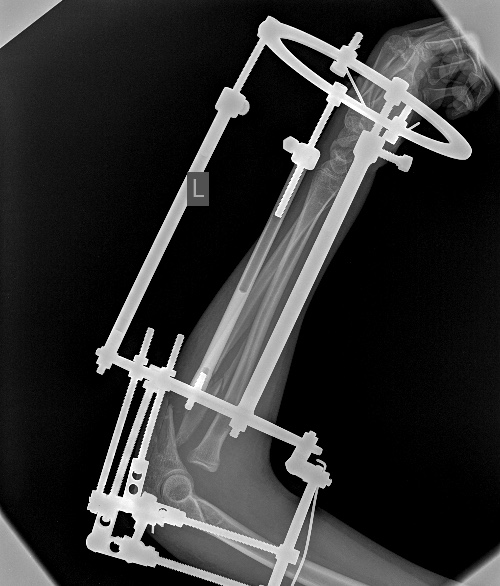

[Ortho] псевдоартроз локтевой с застарелым вывихом радиоульнарного сочленения

Мы бы удалили пластину.  Аппаратом постепенно восстановили бы

взаимоотношения. И заштифтовали бы локтевую кость, смоделировав

стержень, чтобы он был напряжен в противоположную сторону тому, как

сейчас выглядит локтевая кость, т.е. вогнутой стороной в торону

межкостного промежутка. Чтобы лучевая кость удерживалась натяжением

межкостной мембраны. Пример в приложении. Тут был более свежий случай,

поэтому вправилось одномоментно.

Вложение не в текстовом формате было извлечено…

Имя     : 3Предплечье Lat.0001.jpg

Тип     : image/jpeg

Размер  : 110698 байтов

Url     : http://weborto.net:8080/pipermail/ortho/attachments/20141104/6ce4852a/attachment-0007.jpg